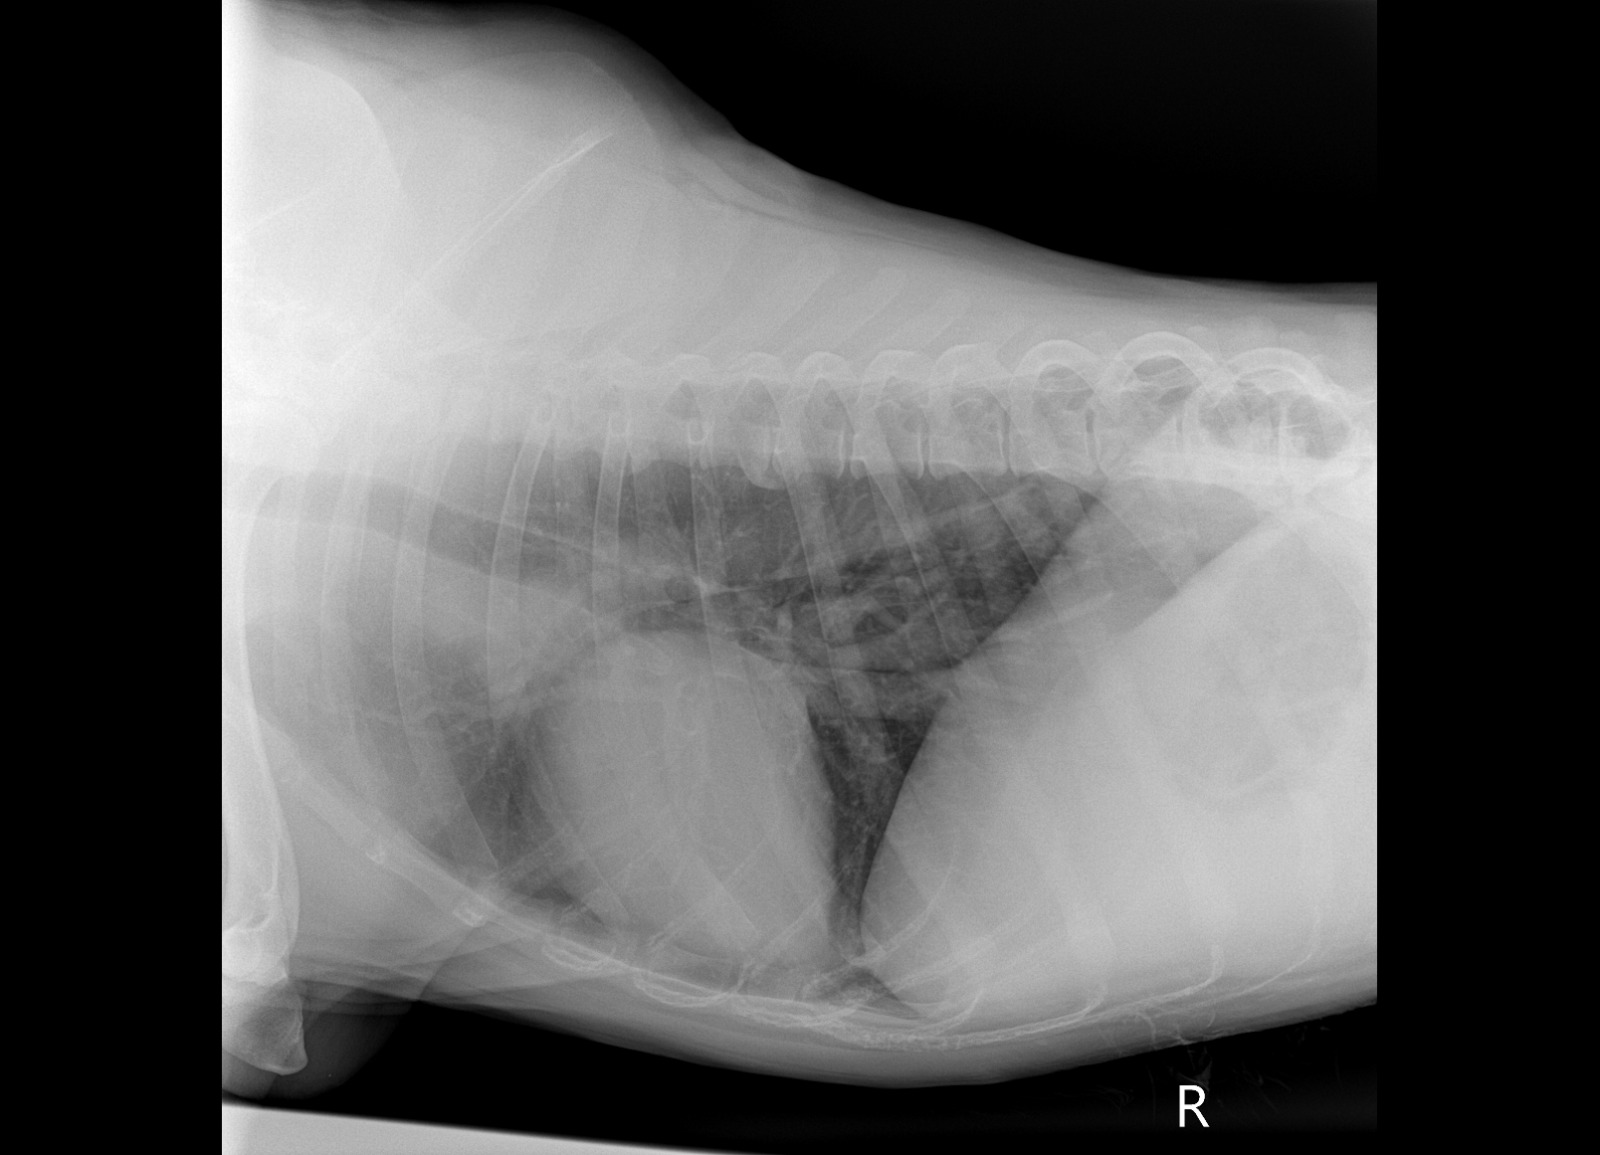

Рентген лапы, которая болит

Зона операции в снимок не попала....но со слов врача все нормально. То что видно - чисто....придется поверить, но так как шов подтекает, антиюиотик попробуем заменить на клиндомицин.

Сильнейший коксартроз тбс на больной лапе.....который не заметили на первичных осмотрах....зато настаивали в необходимости кастрации. В результате изменения положения лапы, нагрузки - воспаление и боль.